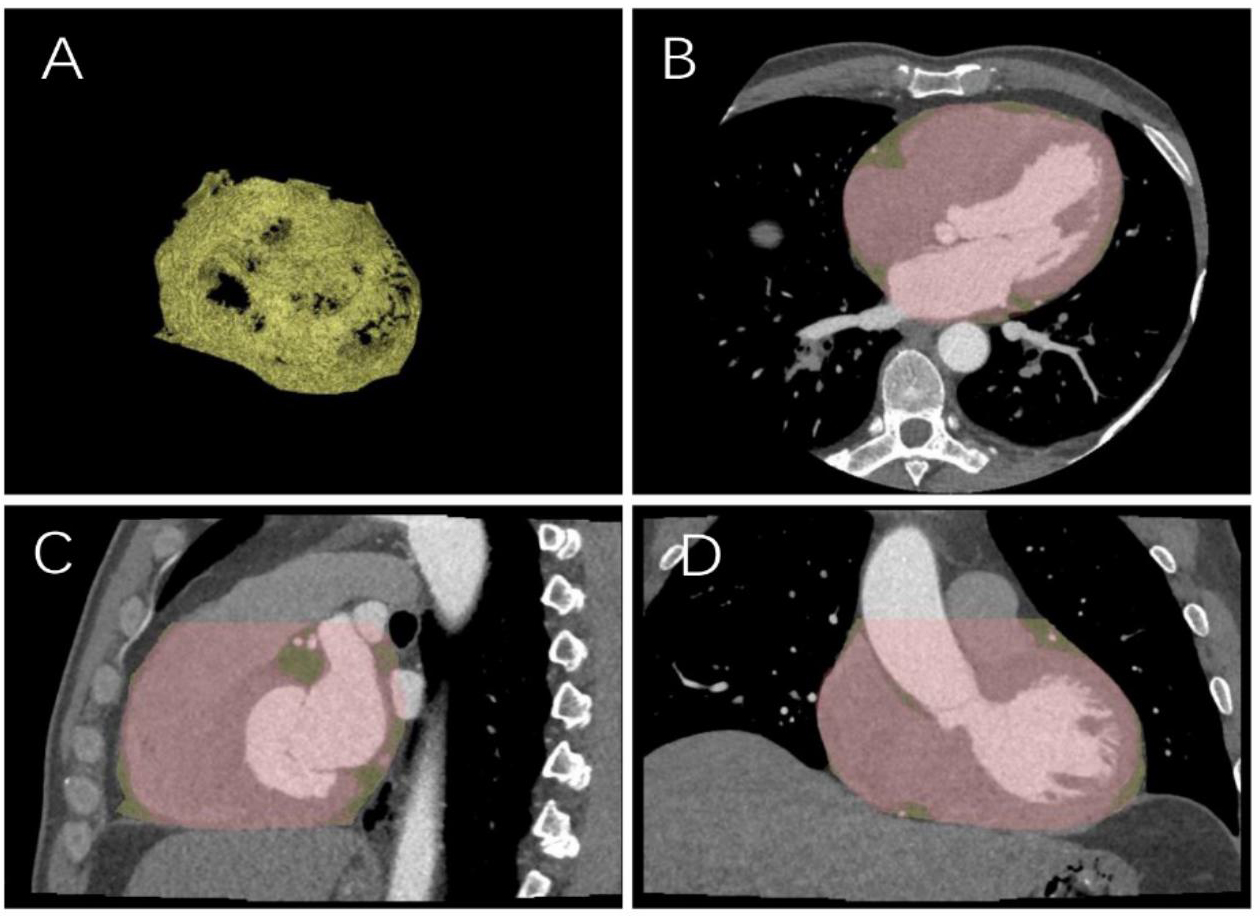

Fig. 2.

Sketch diagram of epicardial fat. (A) Epicardial fat diagram. (B) Axial cardiac image. (C) Sagittal cardiac image. (D) Coronal cardiac image.